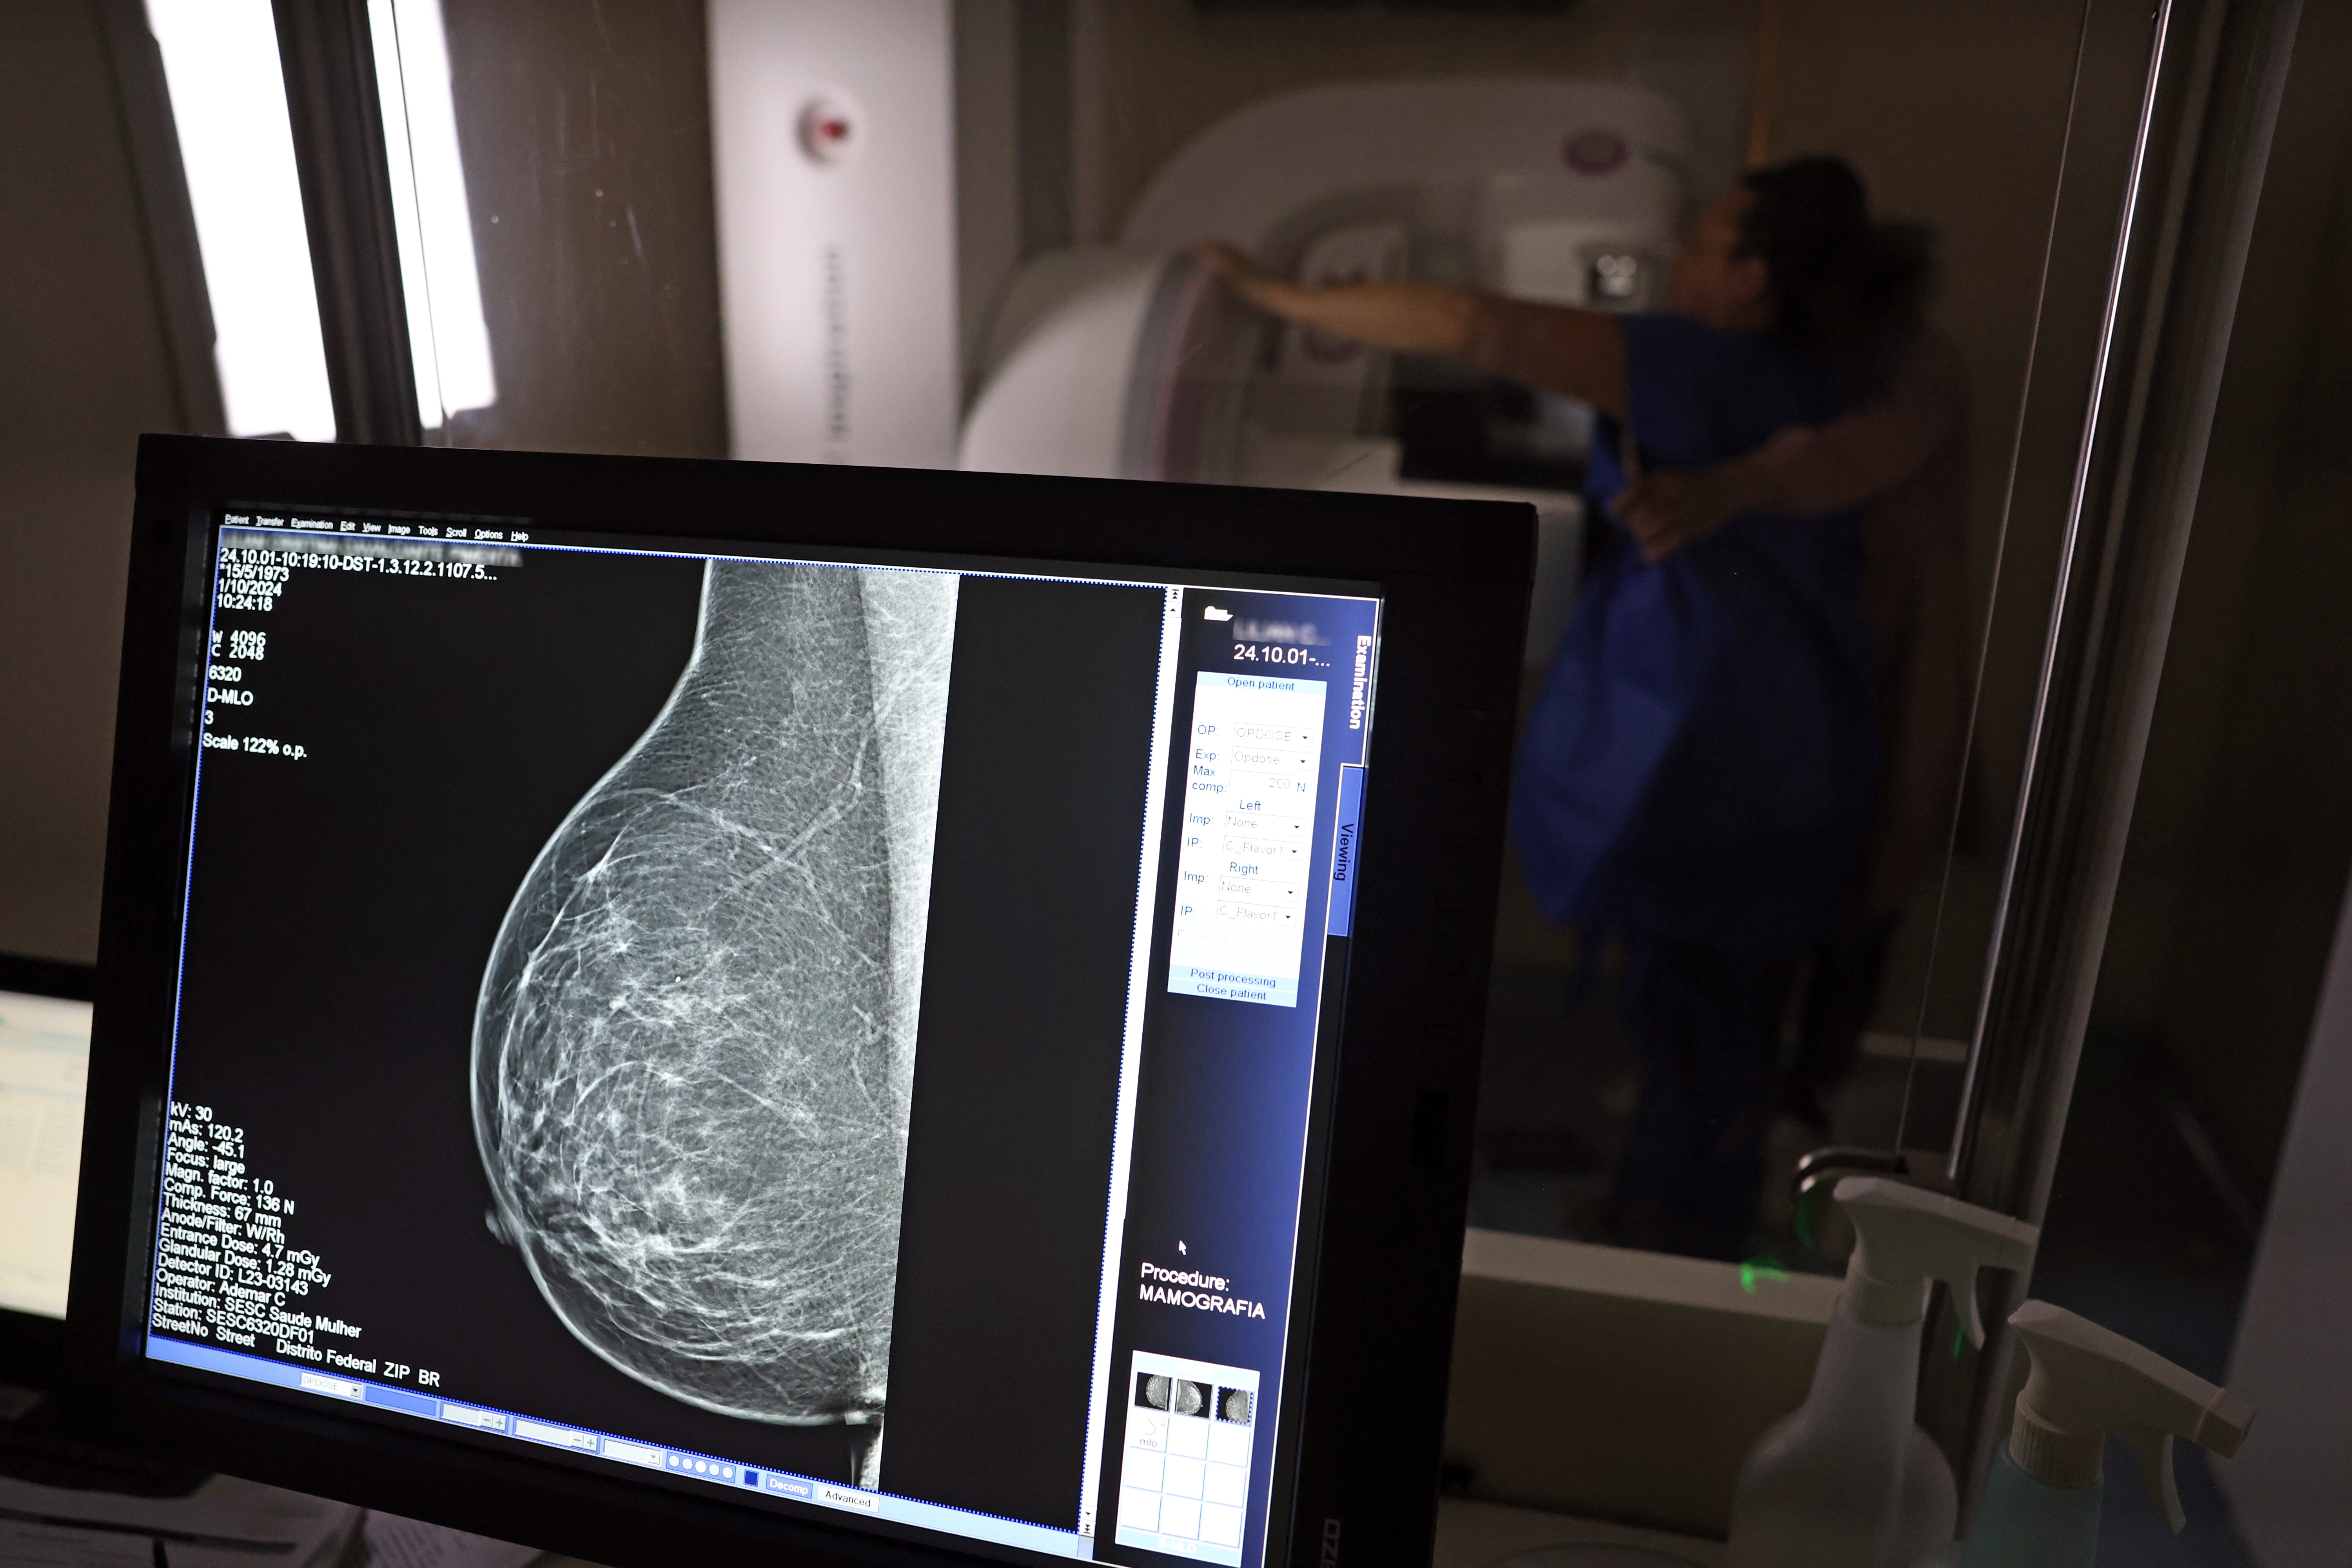

Falta de acesso a mamógrafos limita prevenção do câncer de mama

No mês de conscientização sobre o câncer de mama, um relatório destaca a importância de acesso igualitário ao rastreamento e tratamento da doença. Segundo o Atlas da Radiologia no Brasil, do Colégio Brasileiro de Radiologia e Diagnóstico por Imagem (CBR), o acesso aos mamógrafos ainda é um desafio.

O país tem 6.826 equipamentos registrados, sendo 96% em funcionamento. Metade deles está disponível no Sistema Único de Saúde (SUS), responsável por atender 75% da população. Isso equivale a 2,13 mamógrafos por 100 mil habitantes dependentes do SUS.

Na saúde suplementar, que cobre 25% da população, o cenário é mais favorável: 6,54 aparelhos por 100 mil beneficiárias, quase o triplo da rede pública. O Acre exemplifica essa disparidade — são 35,38 mamógrafos por 100 mil habitantes na rede privada, contra 0,84 no SUS.

O Brasil tem uma cobertura muito baixa de mamografias: 24%. O ideal recomendado pela Organização Mundial da Saúde é de 70%. Mesmo em lugares como o estado de São Paulo, que tem a maior concentração de mamógrafos do país, a taxa gira em torno de 26%.

Em setembro, o Ministério da Saúde ampliou as diretrizes de rastreamento, recomendando que mulheres entre 40 e 49 anos realizem mamografias, mesmo sem sintomas. De acordo com o Instituto Nacional do Câncer (Imca), mais de 73 mil mulheres recebem o diagnóstico de câncer de mama anualmente no Brasil.

“O que é efetivo na redução da mortalidade é você descobrir o tumor antes de ter sintoma clínico. Quanto menor o tumor, melhor para a gente descobrir o tratamento e maior a chance de cura. E a gente só consegue fazer isso com exames de imagem", diz Ivie.

Ela explica que no caso de diagnóstico de um câncer de mama com menos de 1 cm, a chance de cura é de 95% em cinco anos, independentemente se ele é do tipo mais agressivo. "E esses tumores só vão ser detectados na mamografia. Essas pessoas que têm que ir fazer mamografia são mulheres saudáveis. Não são mulheres doentes”, acrescenta.